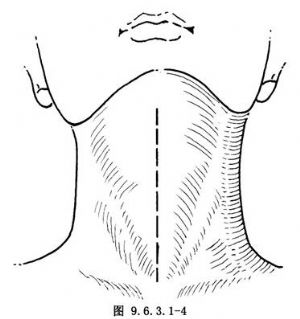

垂直切口,在頸前中線縱行切開,上起自舌骨中點,下達胸骨上切跡(圖9.6.3.1-4),此切口術野窄,需助手用拉鉤牽開暴露。